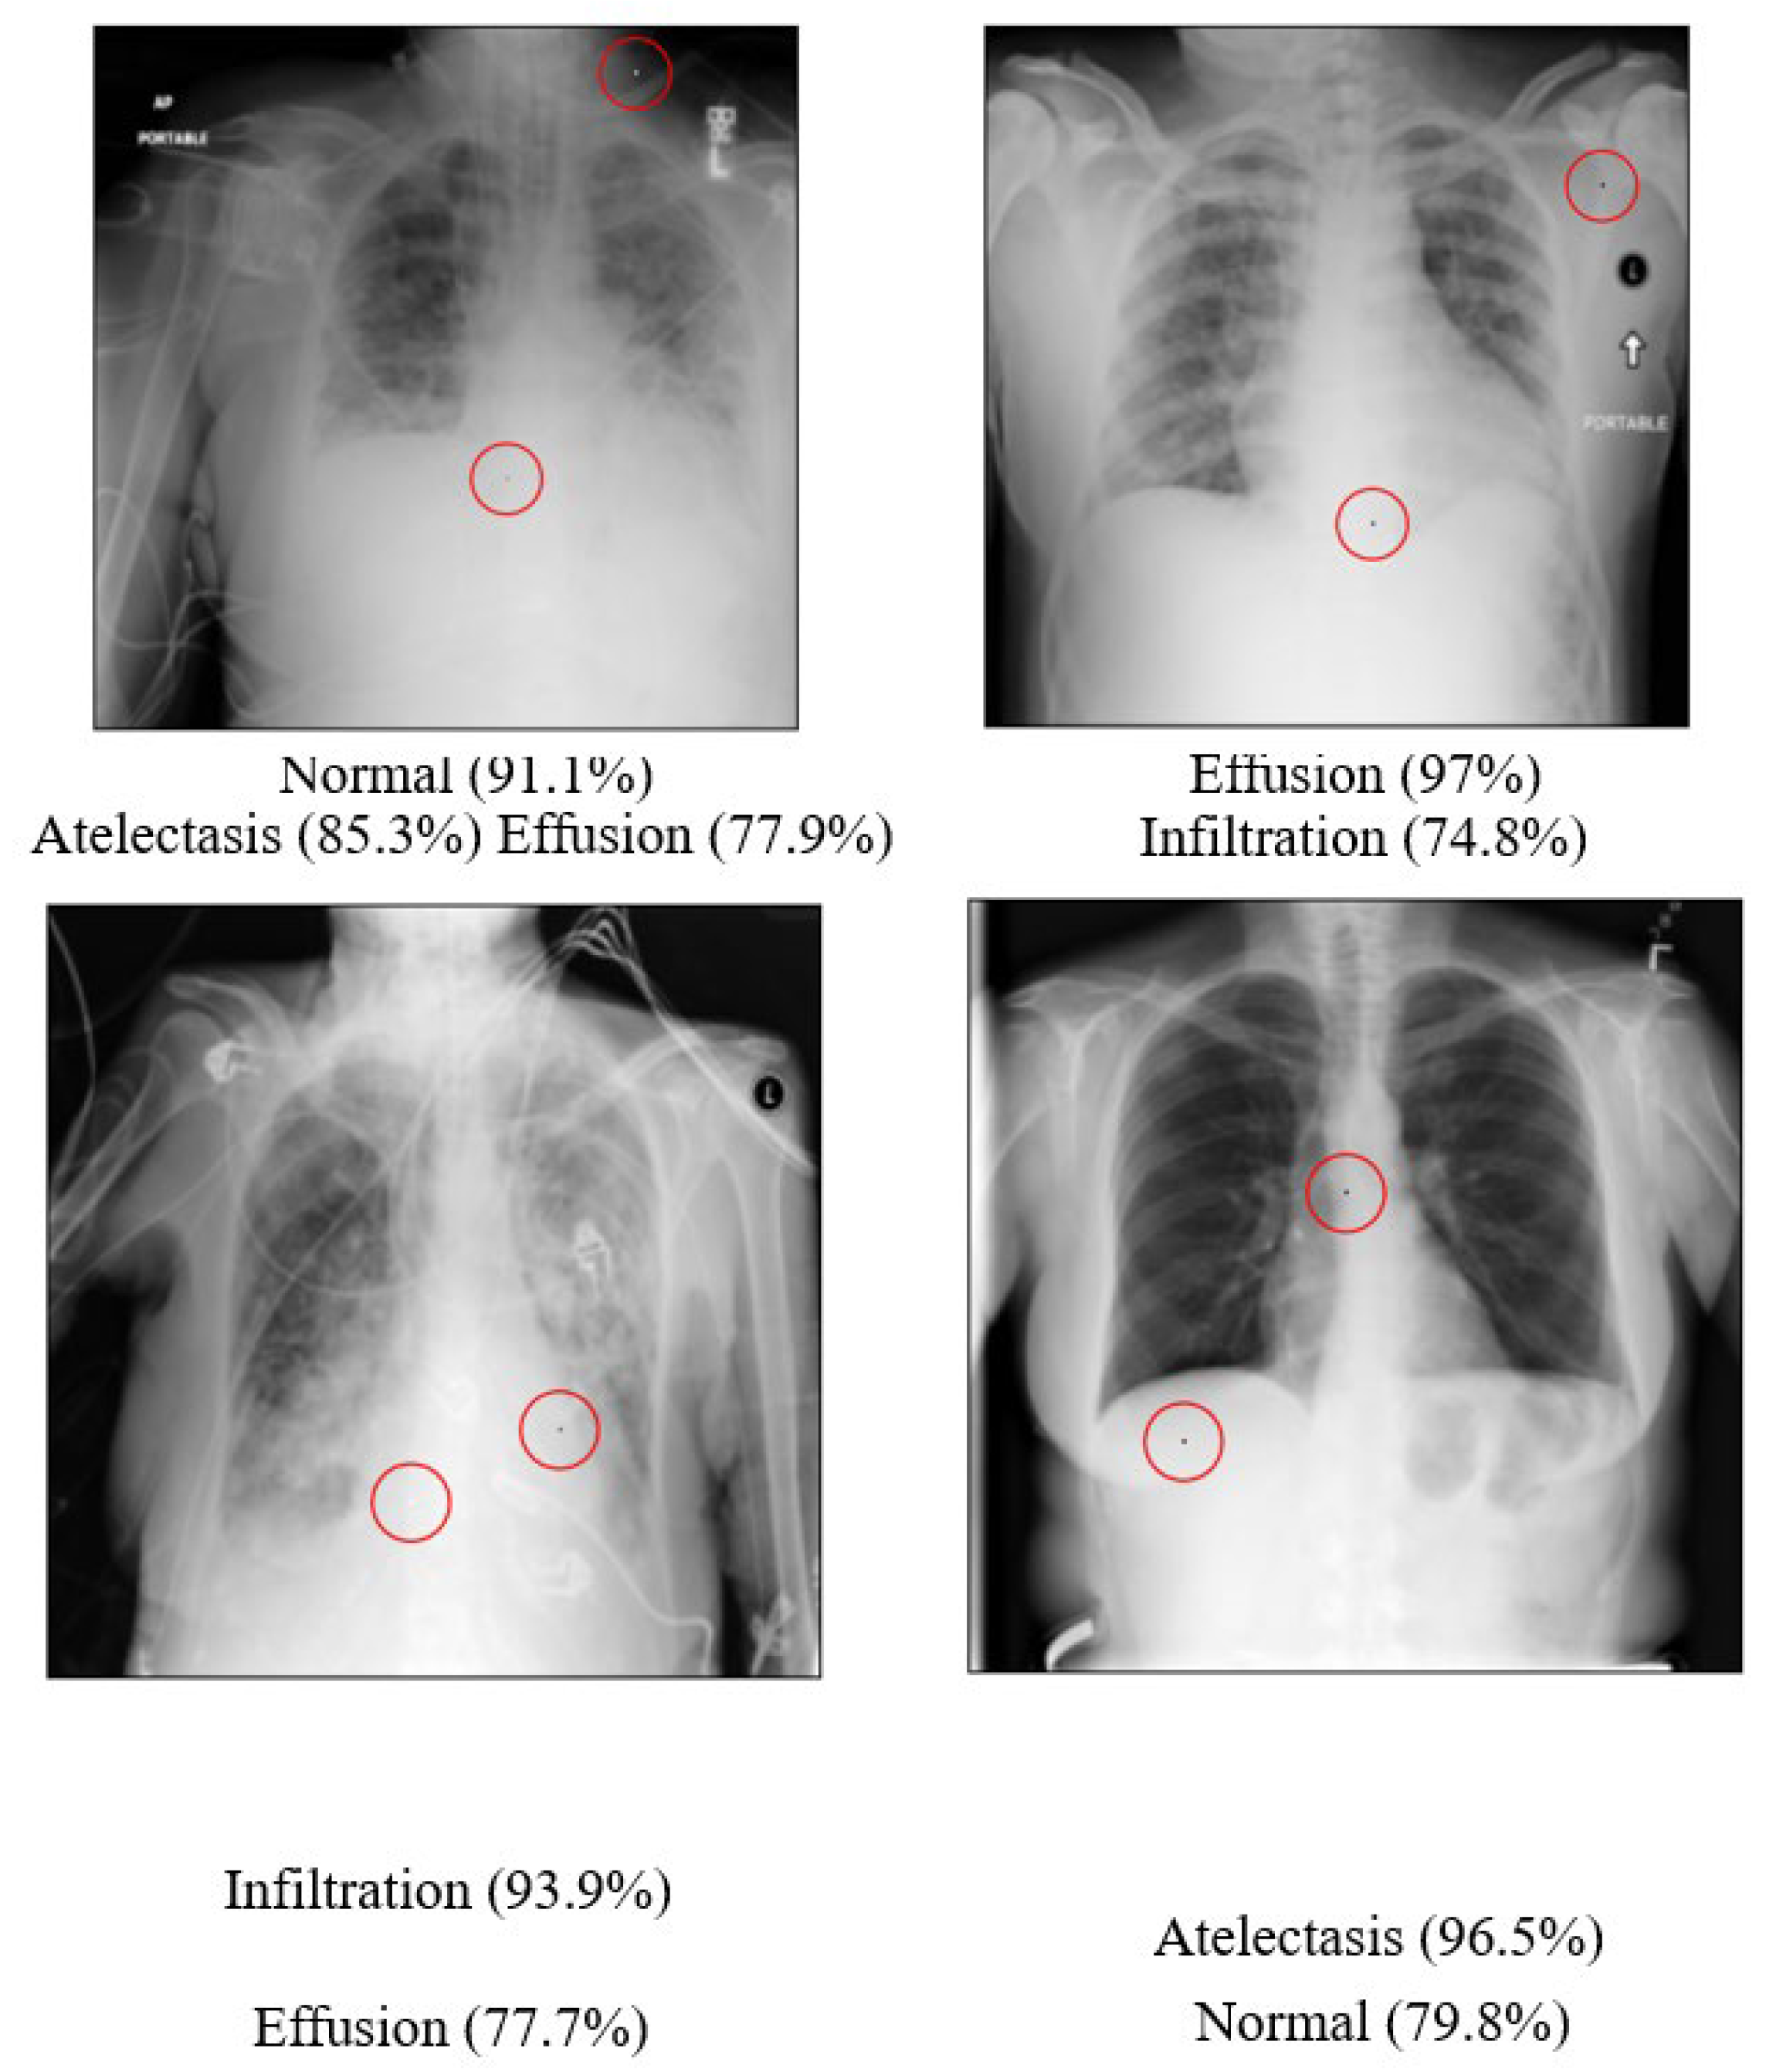

The statistical results of the Two-Pixel attacks on the Chest dataset are presented in Table 30 below. 468 of the total 500 images were successfully attacked and had their categories altered, resulting in an overall success rate of 93.6%. This was an improvement on the 90.43% success rate of One-Pixel attacks. Examples of the successful Two-Pixel attacks on the Chest dataset are shown in Figure 19 below.

The average denoising results for each model on the Chest dataset are shown in Table 31 below. The images of the Chest that were successfully attacked with Two-Pixel attacks are, respectively, shown in Figure 20 below, along with the reconstructed images after being denoised by each model.